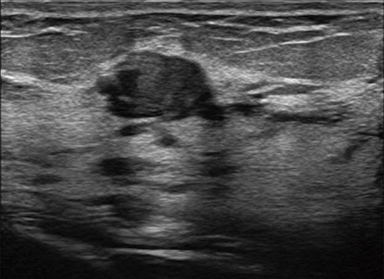

OFF

ON

Analyzes the received signal of each channel in real-time, and suppresses signals that disturb the imaging.

Enhances visualization of tissue boundaries by transmitting beams in multiple directions, thus reducing artifacts experienced when using a single beam path.